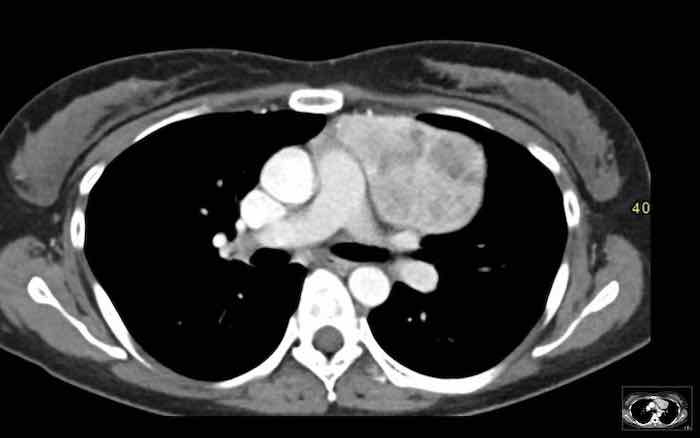

Các hình ảnh này của một phụ nữ 65 tuổi có tiền sử mắc bệnh Graves, một rối loạn tự miễn liên quan đến tình trạng cường chức năng tuyến giáp.

CT được thực hiện vì lý do ho ra máu.

Hình ảnh

Có một tuyến ức to lớn, cồng kềnh chứa mô mỡ đại thể.

Đây là hình ảnh điển hình của tăng sản tuyến ức.

Tăng sản tuyến ức trong bệnh Graves có liên quan đến tình trạng dư thừa hormone tuyến giáp và kháng thể kháng thụ thể thyrotropin.

Tình trạng này thường cải thiện sau khi điều trị thành công bệnh Graves.